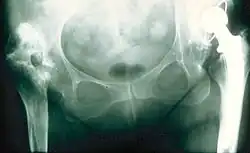

Coxa vara (lateinisch coxa ‚Hüfte‘, varus ‚auswärts gebogen‘) ist ein deskriptiver Begriff für eine nicht normale und nicht altersgemäße Stellung des oberen Endes vom Oberschenkelknochen. Der (schwer messbare) CCD-Winkel liegt unter 126°. Steht der Femurkopf unter dem Trochanter major (CCD < 90°), spricht man von einer Hirtenstabdeformität.

Röntgen

Zur Diagnose und Verlaufsbeurteilung reichen Röntgenaufnahmen. Bei der aussagekräftigen Beckenübersicht im Stand sollten die Füße geschlossen nebeneinander stehen; denn nur dann ist der Seitenvergleich des CCD-Winkels möglich. Die Rotation des Femurhalses ist am besten in der Computertomografie zu sehen. Der Femurkopf drängt zur Pfannenmitte. Diese sog. Zentrierung gefährdet den Boden des Acetabulums. Nur die intertrochantere Valgisierung kann (bei gesundem Knochen) die Protrusio acetabuli verhindern.[3] Diese Korrekturosteotomie ist viel seltener sinnvoll als die intertrochantere Varisierung.